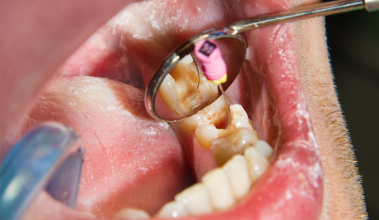

Nyeri akibat gigi berlubang parah dapat segera teratasi, bahkan sejak kunjungan pertama.

Dengan penanganan dokter gigi berpengalaman di Dharmawangsa Dental Studio, perawatan saluran akar dilakukan dengan teknologi modern sehingga nyeri hilang lebih cepat dan pasien merasa nyaman.